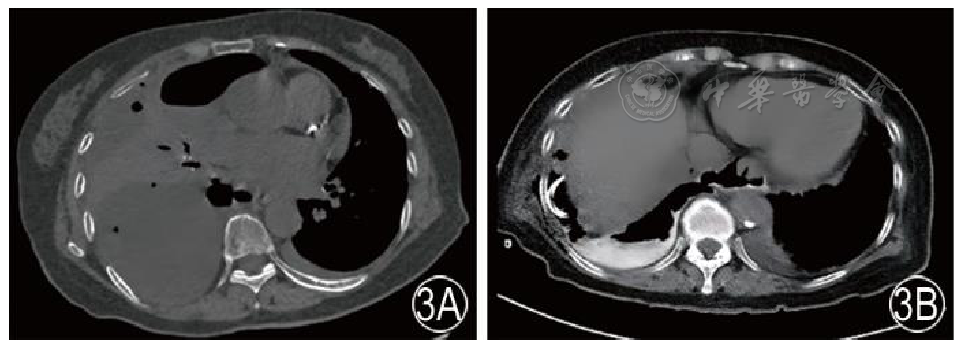

图3 术后复查CT 3A 腹腔镜食管裂孔疝术后第7天CT检查,见右侧胸腔积液较之前的影像明显增多,并伴有气体密度,同时可见相邻肺组织的明显压迫。膈肌区域出现气体和液体积聚,不能排除食管下段瘘的可能。3B 口服造影剂后CT检查(术后第8天)示食管下段存在瘘管,并且对比剂渗漏进入右侧胸腔